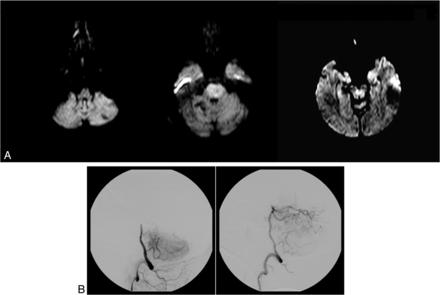

Prethrombectomy DWI (A) of a 54-year-old woman with tetraplegia in a coma. The DWI shows extensive bilateral lesions in the pons and limited bilateral lesions in the midbrain (brain stem score, 2 + 2 +1 + 1 = 6). DSA shows a midbasilar occlusion (B) successfully recanalized after IV thrombolysis and a thrombectomy (TICI 3). Time from symptom onset to recanalization was 283 minutes (4 hours 43 minutes). The outcome was unfavorable by day 180 (mRS 5).